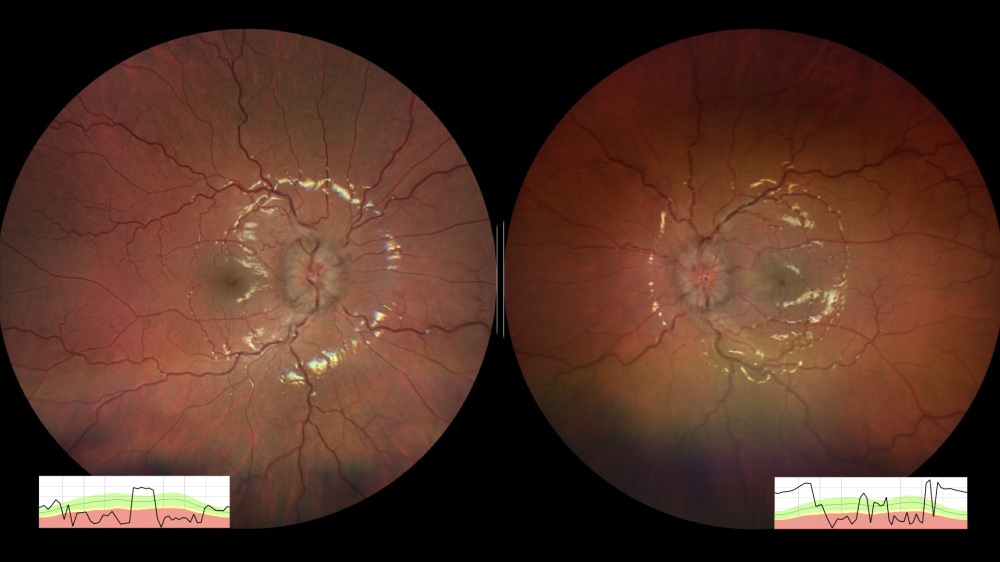

Título: Popcorn! At The Disc(o)

Autor: Ricardo Marques Mocho

Coautores: Laura Vilaverde, Pedro Baptista

Instituição: ULS de Santo António

Descrição: Multimodal Imaging (Wide-Field Retinography, Fundus Fluorescein Angiography and Fundus Autofluorescence) of a peripapillary astrocytic hamartoma